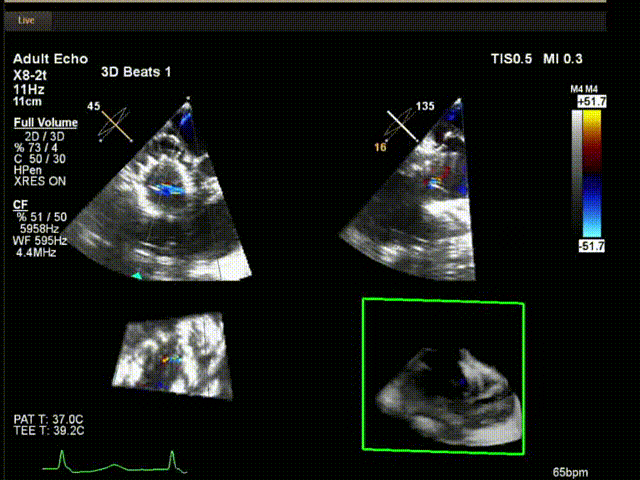

術(shù)中超聲

陸方林教授通過(guò)遠(yuǎn)程線上帶教的方式,與林逸賢教授團(tuán)隊(duì)共同完成了此次LuX-Valve Plus人工瓣膜的首例植入。術(shù)后食道超聲提示三尖瓣反流完全消失,無(wú)瓣周漏,且LuX-Valve Plus人工瓣膜的兩個(gè)夾持鍵成功抓取瓣葉,錨定牢固,人工瓣膜穩(wěn)定性良好。

手術(shù)在全麻狀態(tài)下開(kāi)展,此次手術(shù)采用經(jīng)頸靜脈入路的方式。在TEE及DSA雙重引導(dǎo)下,術(shù)者調(diào)整輸送器頭端角度使得其與三尖瓣瓣環(huán)平面垂直。在輸送器進(jìn)入右心室后釋放室間隔錨定裝置,而后釋放瓣葉夾持件(2個(gè)耳片結(jié)構(gòu))成垂直狀態(tài)。在TEE及DSA確定夾持件固定至三尖瓣葉根部且位于右室側(cè)后釋放人工瓣心房側(cè)盤(pán)片。隨后調(diào)整瓣膜同軸性以及室間隔錨定件位置(貼合室間隔),進(jìn)而釋放室間隔錨定裝置,并再次確認(rèn)瓣膜位置、穩(wěn)定性及同軸性,解離人工瓣膜與輸送器間連接,并撤出輸送器,完成了LuX-Valve Plus人工三尖瓣瓣膜的植入。